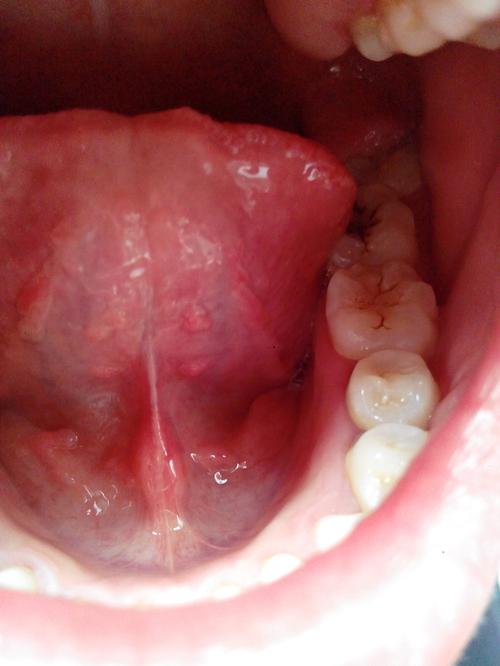

这是最直接的反应,通常表现为口腔内出现单个或多个的赘生物。

- 菜花状:最典型的形态,像小菜花一样,表面凹凸不平,有多个细小的指状突起。

- 乳头状:表面呈乳头样,颗粒粗糙。

- 丘疹状:初期可能表现为单个或多个小的、淡红色或肤色的小丘疹,质地柔软。

- 斑块状:有时也可能表现为表面光滑的扁平斑块。

- 通常呈粉红色、白色、灰色或浅褐色,颜色与周围黏膜相近,有时不易察觉。

(图片来源网络,侵删)- 舌下系带:这是最常见的部位之一。

- 口底:舌头下方区域。

- 软腭:口腔上后方软的区域。

- 唇、颊黏膜、牙龈:也可能发生,但相对较少。